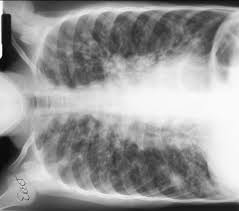

Fibrosis, the forming of scar tissue, can be a genetic disease commonly seen in the lungs as cystic fibrosis and idiopathic pulmonary fibrosis, according to ... read more

For the first time in history, cystic fibrosis patients are getting old. What once was a disease that claimed most victims in childhood, many cystic ... read more